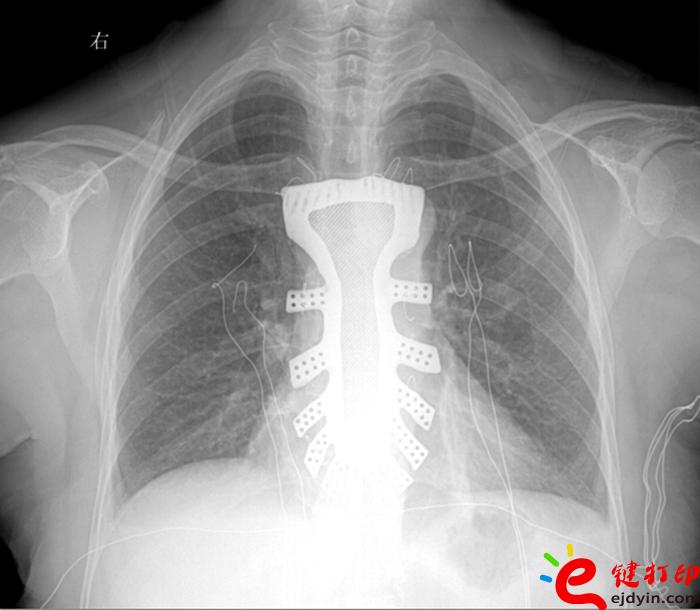

3D打印鈦合金胸骨植入術(shù)

據(jù)王小平教授介紹,唐都醫(yī)院3D打印小組經(jīng)過精密計(jì)算患者胸骨的大小、形狀等,充分研究討論,歷時(shí)一周,為患者設(shè)計(jì)出了手術(shù)使用的3D胸骨模型,并與西北工業(yè)大學(xué)凝固技術(shù)國家重點(diǎn)實(shí)驗(yàn)室合作,為患者打印出了1:1鈦合金胸骨模型。隨后,又對該模型進(jìn)行了一系列嚴(yán)密的醫(yī)學(xué)處理。

“手術(shù)歷時(shí)2.5小時(shí),對患者的胸骨進(jìn)行了整體切除,置換了鈦合金胸骨,目前患者恢復(fù)良好,未發(fā)現(xiàn)任何并發(fā)癥?!蓖跣∑浇淌诜Q,根據(jù)專業(yè)機(jī)構(gòu)檢索,該手術(shù)是世界首例針對胸骨腫瘤疾病,將3D打印的可植入性鈦合金胸骨植入人體,實(shí)現(xiàn)病變胸骨的整體置換的手術(shù)。該手術(shù)的成功意味著未來將會(huì)為更多的胸骨腫瘤患者帶來福音。

“現(xiàn)在感覺和生病前沒什么區(qū)別。”7月8日,記者在唐都醫(yī)院病房見到顧女士時(shí),她氣色很好,有說有笑。除了胸前留下一條長長的疤痕外,從外表看與健康人沒什么兩樣。

參與此次3D鈦合金胸骨設(shè)計(jì)的唐都醫(yī)院3D打印團(tuán)隊(duì)王臻博士表示,此次嘗試是3D打印技術(shù)與外科手術(shù)的一次完美結(jié)合。3D打印的個(gè)性化服務(wù)與醫(yī)學(xué)有著天然的聯(lián)系,目前3D打印技術(shù)在醫(yī)學(xué)上的研究越來越廣泛,為醫(yī)學(xué)的未來發(fā)展提供了無限可能。